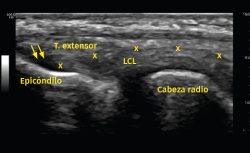

Otro método utilizado es la ecografía, que permite detectar cambios estructurales que afectan a los tendones (engrosamiento, adelgazamiento, áreas degenerativas intrasustancia y desgarros del tendón, por ejemplo), irregularidades óseas o depósitos de calcio(6)(Figura 6). Además, la exploración con Doppler color permite valorar la presencia de neovascularización (Figura 7). La ausencia de este hallazgo o de cambios en la estructura del tendón en las pruebas de imagen debe hacer dudar sobre el diagnóstico de tendinopatía lateral del codo(15). Tiene la ventaja de poder relacionar los síntomas del paciente con los hallazgos ecográficos en tiempo real pero, por otro lado, es operador-dependiente(12). Los estudios demuestran que esta prueba presenta una alta sensibilidad (72-88%), pero una baja especificidad (36-48,5%)(16).

Figura 6. En este examen longitudinal del tendón extensor común (T. extensor), se describen los signos ecográficos de una epicondilopatía: el aumento de grosor del tendón y la pérdida de su patrón fibrilar con áreas de pequeña rotura en su interior (flechas). Imagen cedida por el Dr. Fernando Jiménez Díaz.

Figura 7. En otra imagen del mismo paciente, al aplicar el Doppler potencia se aprecia un aumento de la vascularización. Imagen cedida por el Dr. Fernando Jiménez Díaz.